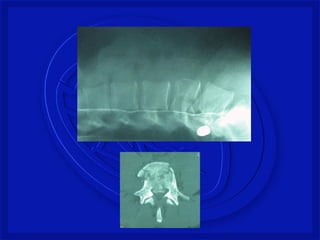

FRATURA COMPRESSÃO TORÁCICA

BAIXA

LESÕES - COLUNA